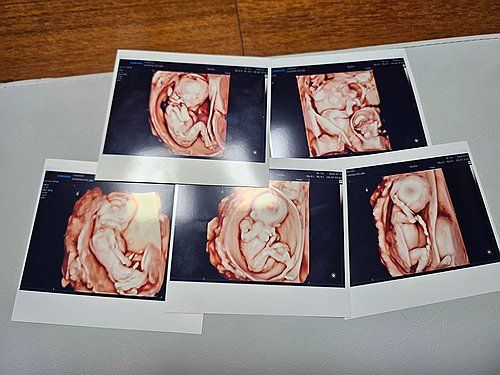

서울성모병원서 다섯쌍둥이 탄생 서울성모병원서 다섯쌍둥이 탄생

서울성모병원은 지난 9월 20일 낮 남자아이 3명과 여자아이 2명의 '오둥이'가 건강하게 태어났다고 밝혔다. 사진은 오둥이의 초음파 사진. [서울성모병원 제공. 연합뉴스 자료사진. 재판매 및 DB 금지]